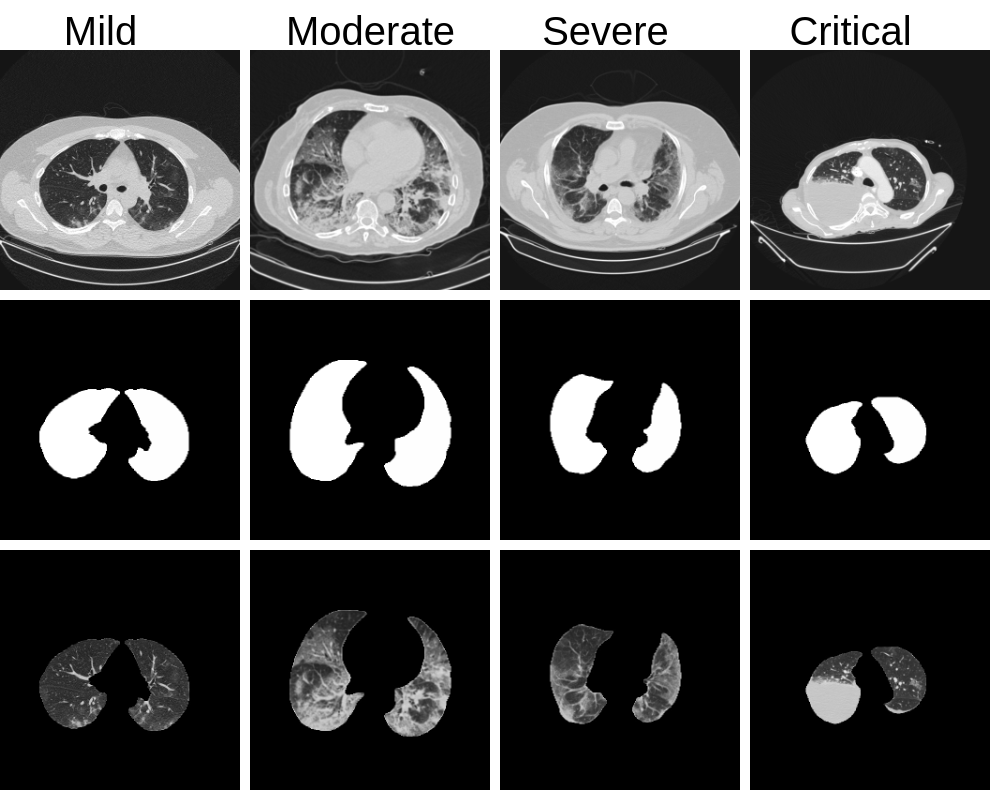

Fig. 1: First row represents CT scan images of mild, moderate, severe, and critical categories provided in the challenge. The second row shows the lung mask generated from the images. The third row depicts the segmented region of interest for further analysis of each category.

The lung mask involvement accounts for variations in the number of CT image slices across patients. An empirical threshold on the lung mask’s involvement and a threshold on the number of slices from the middle region (slice number which lies between one-third to two-thirds of the total number of slices) are used to select the CT scan images for further analysis. The region of interest is extracted using the lung mask from the chest CT scan images. The segmented CT scan images are applied with a Gaussian filter to smooth the image without significantly reducing the sharpness of the edges. Further, this image is fed to the image enhancement module. The lung masks and extracted regions of interest from different categories of COVID-19 severity are shown in Fig. 1.